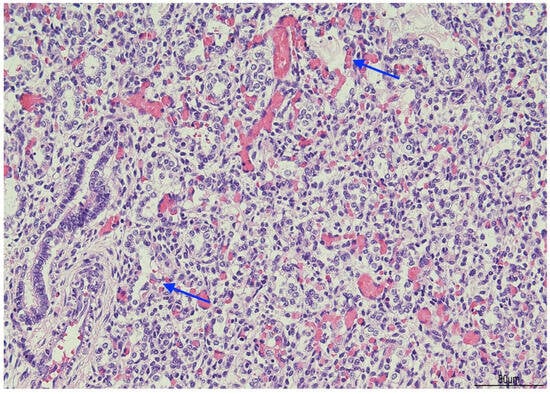

Background: The purpose of this study was to examine the relationship between qualitative characteristics and quantitative parameters from contrast-enhanced ultrasound (CEUS) and microvessel density (MVD) in hepatoblastoma (HB), as well as to investi...